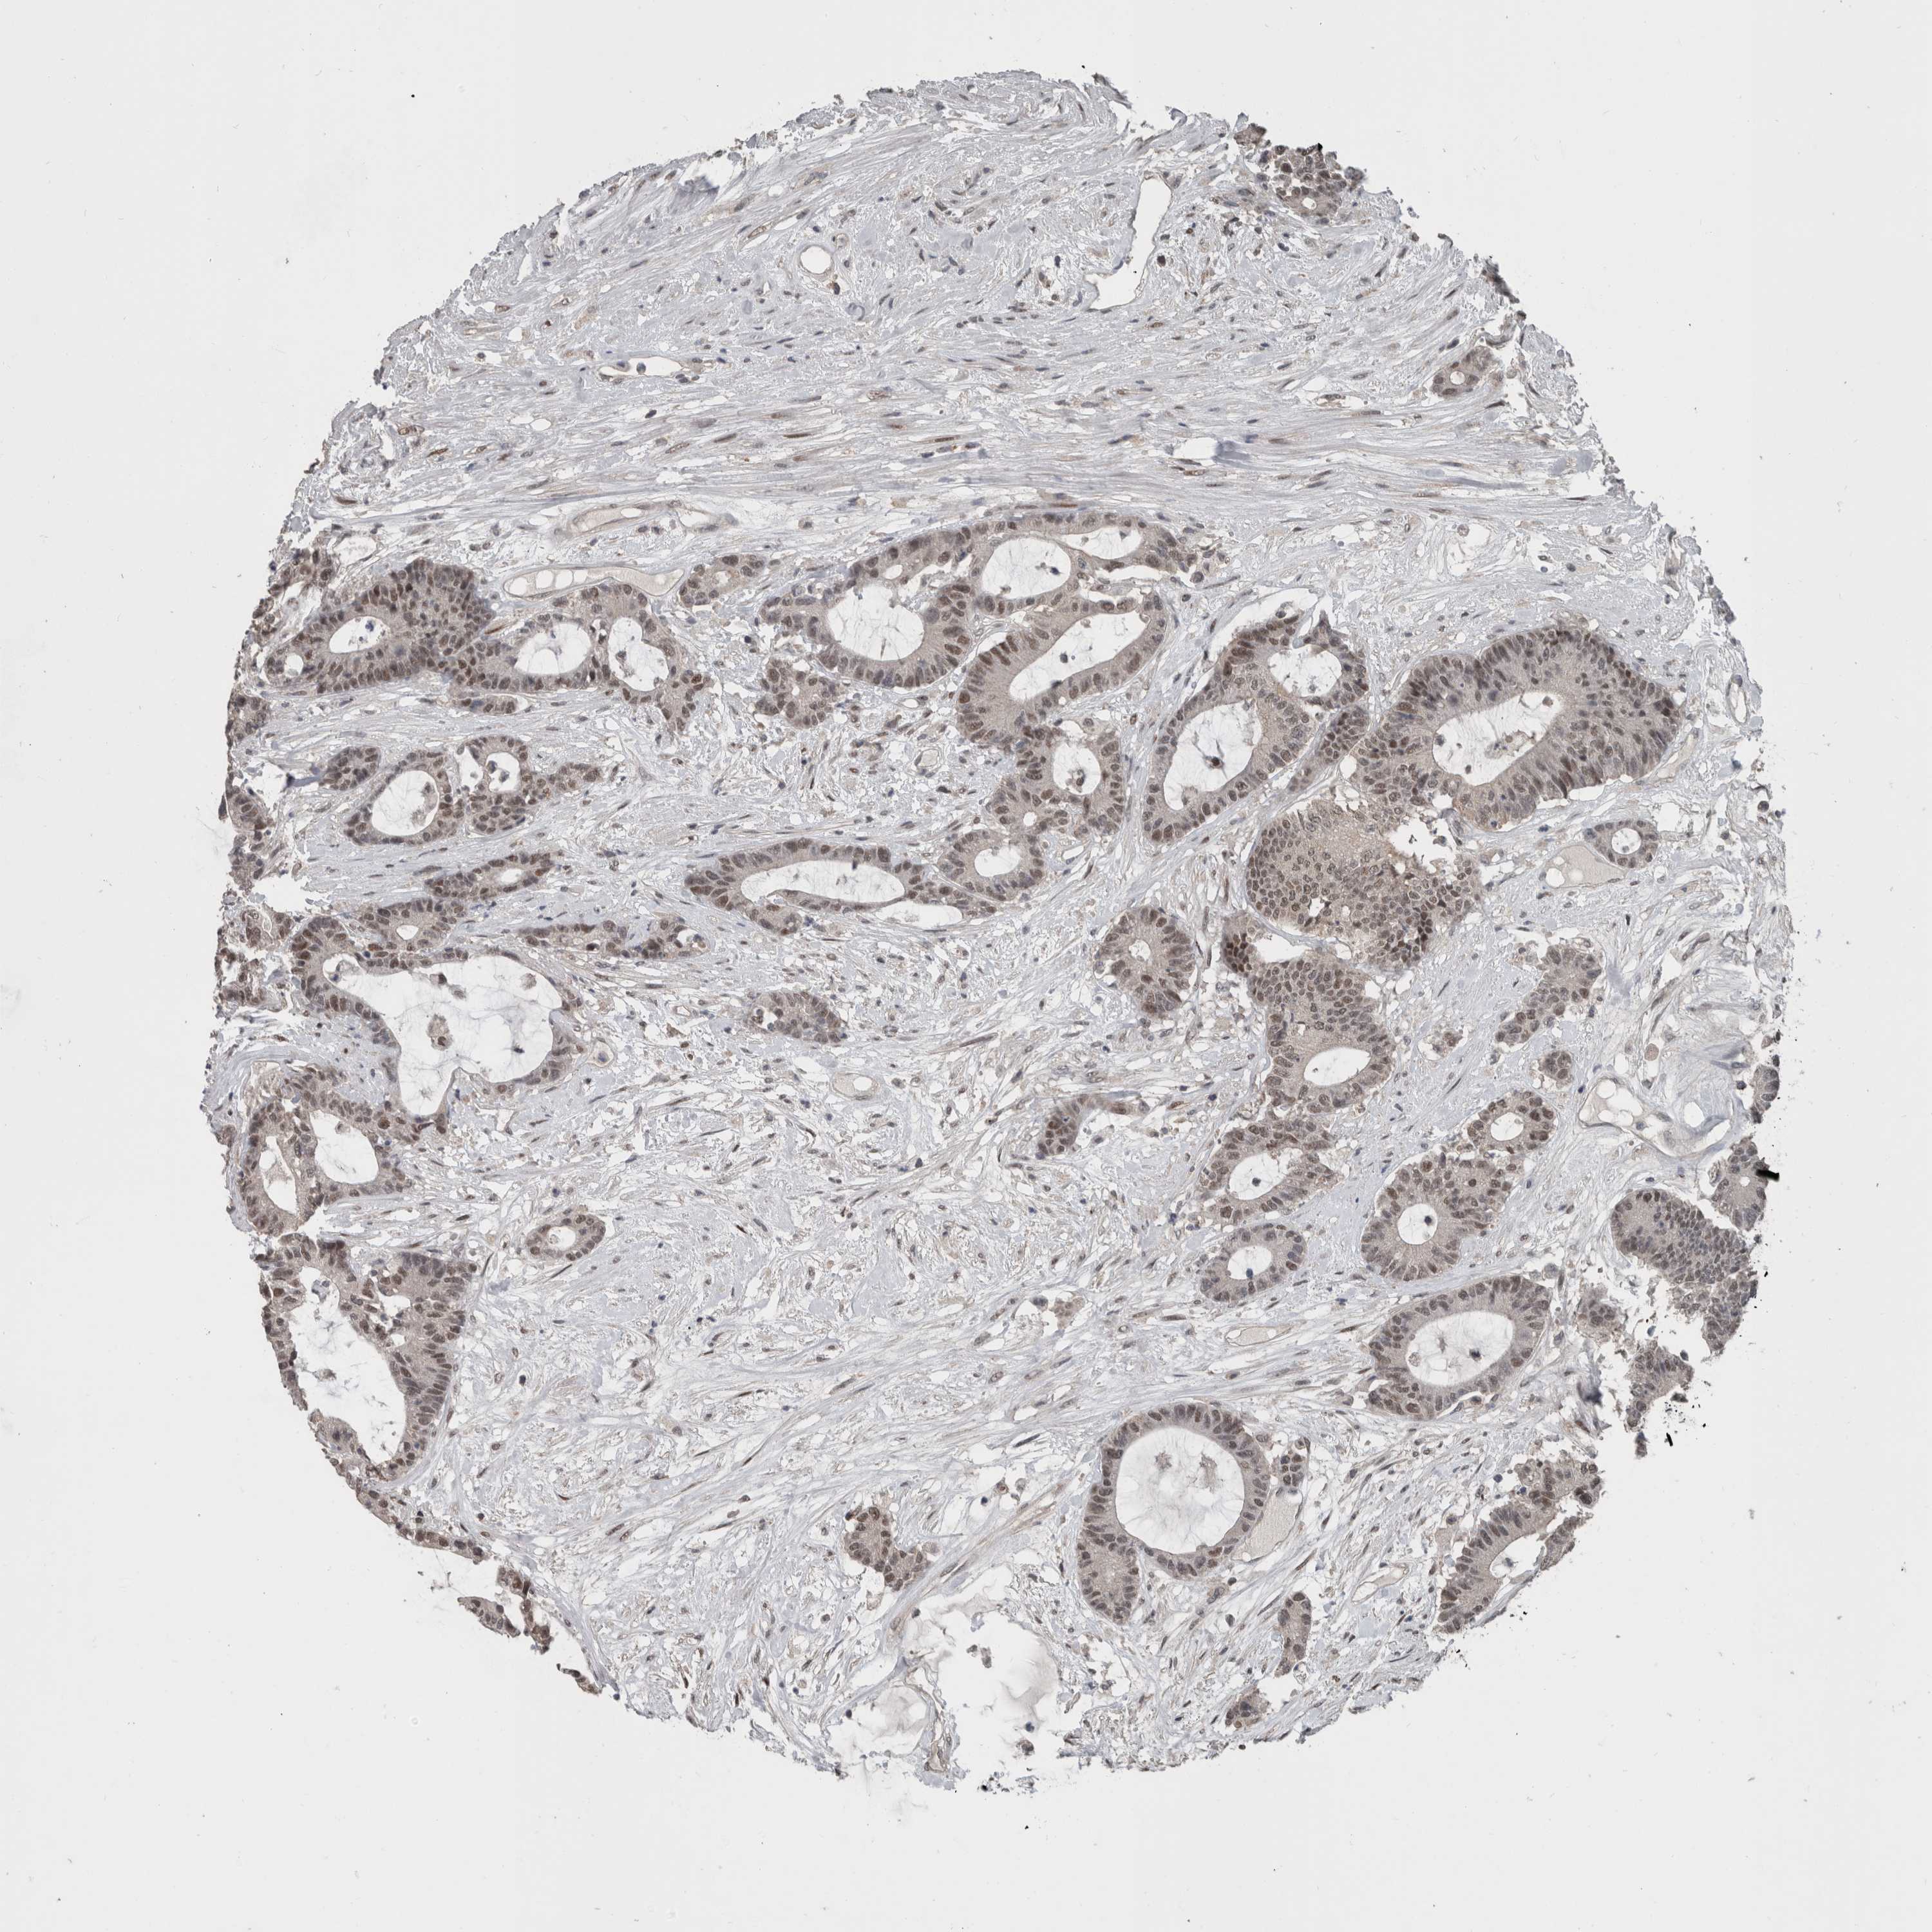

CANCER COLORECTAL CANCER Show tissue menu

Colorectal cancer

Human cancer

Colon adenocarcinoma